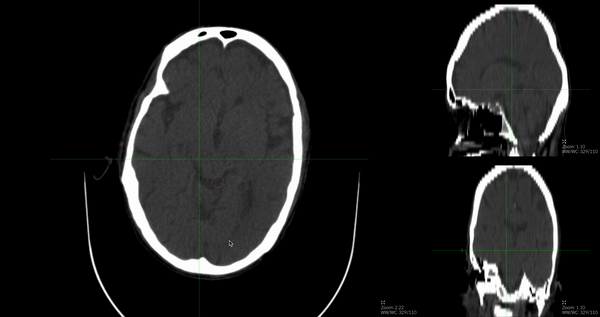

### Description Folks, I implemented a plugin brush tool that shows segmentation of axial, coronal, and sagittal simultaneously. This uses [cornerstone-side-image-loader](https://github.com/plantarflex/cornerstoneSideImageLoader) which was also implemented to do multiplanar-reconstruction(MPR) new sagittal...

I implemented a synchronized brush for stacked images that shows real-time segmentation of axial, coronal, and sagittal views. It goes like this:  This inherits BaseBrushTool of latest version, but...